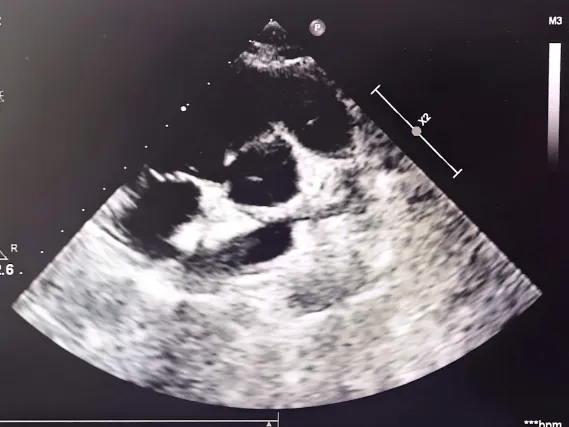

右心声学造影

静息状态:单帧图像气泡约20个(II级)

-

右房增压状态:第1个心动周期开始出现气泡,即刻充满左心(III级)